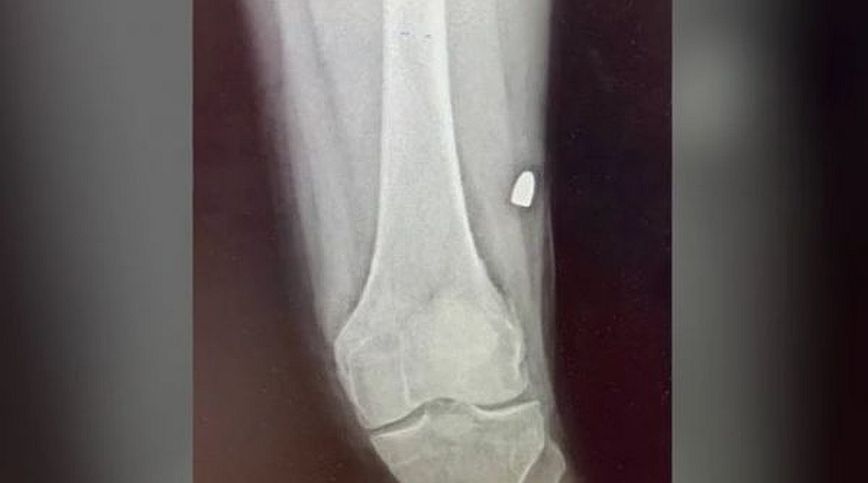

Το MEGA δημοσίευσε και φωτογραφία που δείχνει τη σφαίρα των εννέα χιλιοστών μέσα στο σώμα του θύματος.

Οι γιατροί την αφαίρεσαν και την έστειλαν στα εγκληματολογικά εργαστήρια της ΕΛ.ΑΣ.